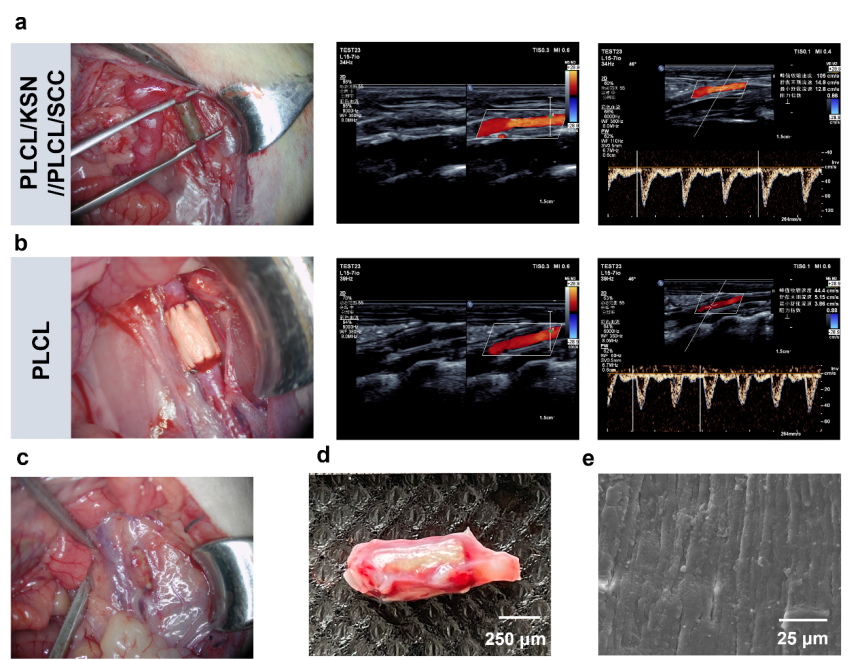

在大鼠模型中,移植1个月后超声检测显示,移植物血流通畅,血流速度与天然血管相当,且形成了连续、成熟的内皮层和结构良好的平滑肌层,实现了功能性血管再生。

图9:移植一个月后双层移植物的移植图像、超声图像、宏观图像和扫描电子显微镜图像。